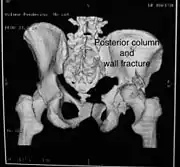

Posterior column and wall fracture as seen on 3D CT

Both column fracture showing floating weight bearing dome